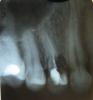

dolceragazza Опубликовано 15 марта, 2010 Поделиться Опубликовано 15 марта, 2010 Добрый день. Заранее извините за дилетантский стиль изложения давно -давно были удалены нервы из 4-ки. зуб стал беспокоить. сделала снимок, доктор открыла зуб, сказала что там перфорация ( вроде бы так) , десна проросла в зуб, из-за этого началось нагноение. почистила, прижгла. через 2 дня сломалась одна стенка зуба. оставшаяся начала шататься. доктор говорит, что можно попытаться протезировать, но говорит, что вся эта конструкция может продержаться недолго, и советует удаление и последующую имплантацию. посоветуйте, пожалуйста, как поступить Ссылка на комментарий

Sir Edward'S Опубликовано 15 марта, 2010 Поделиться Опубликовано 15 марта, 2010 (изменено) а Вы не подскажете, здесь возможно удаление и одномоментная имплантация? и требуется ли синус-лифтинг? о возможности однономоментной имплантаци- станет ясно после удаления,хотя в принципе возможна.по снимку сложно измерить расстояние возможно потребуется закрытый синуслифтинг Изменено 15 марта, 2010 пользователем Sir Edward"S Ссылка на комментарий

x3m Опубликовано 15 марта, 2010 Поделиться Опубликовано 15 марта, 2010 (изменено) 100% удаление. ловить там нечего.имхо, одномоментно -вроде можно. смотреть во рту надо. синуслифт не нужен.(опять же, в идеале правильные, не искаженные расстояния-размеры можно увидеть на КТ) Изменено 15 марта, 2010 пользователем x3m Ссылка на комментарий